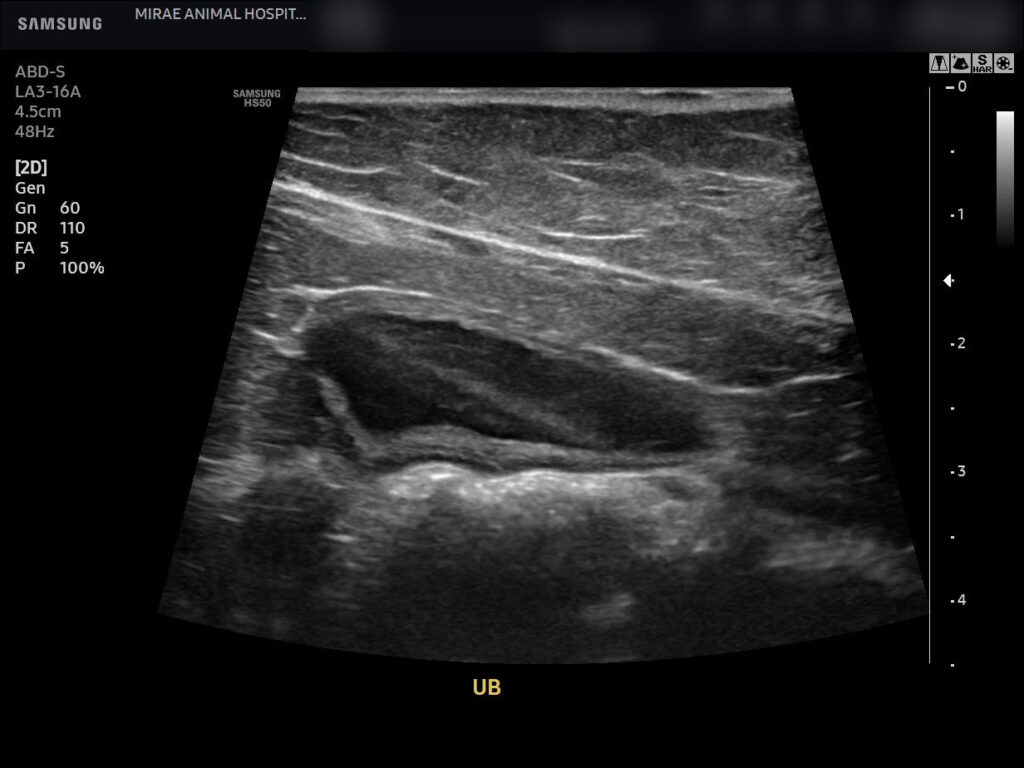

이어 시행한 복부 초음파 검사에서는 방광 내부에 다량의 슬러지가 관찰되었고, 슬러지가 방광 내에 넓게 분포된 상태였습니다.

방광 팽대 역시 매우 뚜렷하게 확인되었습니다. 다행히 양측 신장은 수신증 소견 없이 형태와 구조가 양호한 상태로 평가되었습니다.

환자의 복부 초음파 검사 / 출처: 미래동물의료센터

퇴원 일주일 후 방광 초음파 재진 검사를 시행했습니다. 검사 결과 방광 내부에 슬러지가 경미하게 남아 있는 소견은 확인되었지만자발 배뇨가 원활하게 유지되고 있었습니다.

퇴원 일주일 후 방광초음파 검사 / 출처: 미래동물의료센터